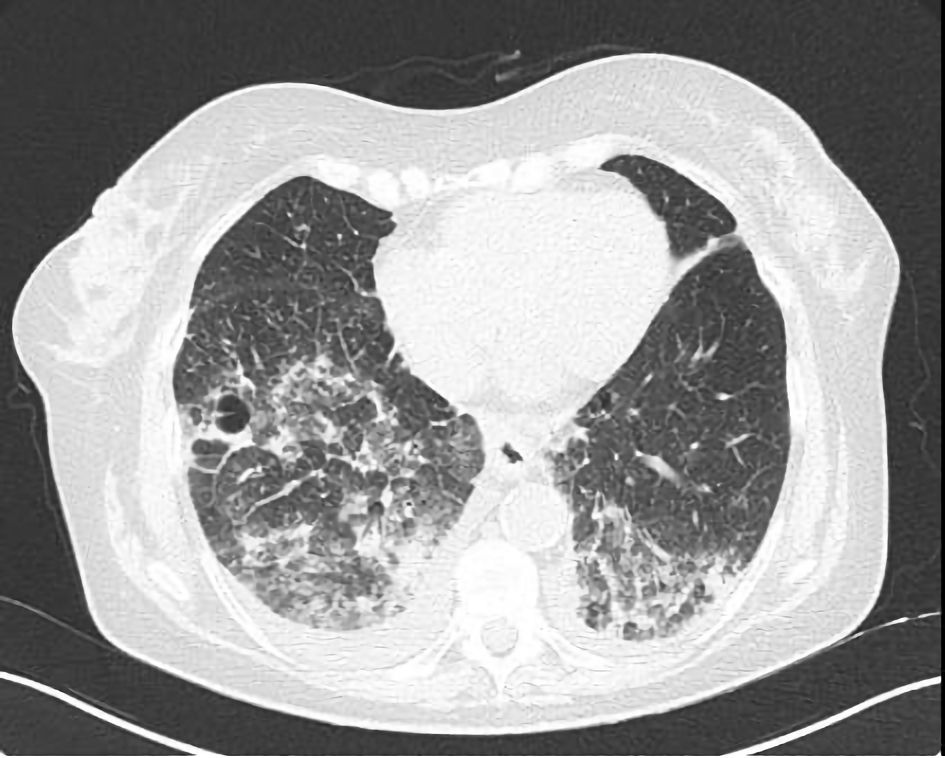

Supporting this hypothesis, the initial CT scan in the emergency department revealed fibrotic streaks in the middle lobe and lingula, along with thickened intralobular septa with a fibrotic appearance at the apices, in addition to the previously noted consolidations. A subsequent high-resolution computed tomography (HRCT) demonstrated the expansion of the previous consolidations in the apical and posterior regions of the upper lobes and the basal regions of the lower lobes, predominantly on the right. New ground-glass opacities and a crazy-paving pattern in the upper and lower lobes were also evident (Fig. 2).

Figure 2. Chest computed tomography scan showing ground-glass opacities, pleural effusion and a crazy-paving pattern in both the lower lobes.

Radiologically, the most frequently reported findings of ICI-related pneumonitis are that of cryptogenic organizing pneumonia, with ground-glass or consolidative opacities in peripheral or peribronchial distribution, followed by nonspecific interstitial pneumonia, with ground-glass opacities and reticular opacities primarily in the peripheral and lower lungs, with or without pleural effusion [13, 21, 24]. In our patient, after contrast-enhanced CT, a confirmation HRCT showed bilateral consolidations, ground glass opacities, and a crazy-paving pattern, consistent with pembrolizumab-induced organizing pneumonia. The radiological appearance of coronavirus disease 2019 (COVID-19) and ICI-induced pneumonitis may be similar [26]. In our case, COVID-19 was excluded immediately by PCR testing.